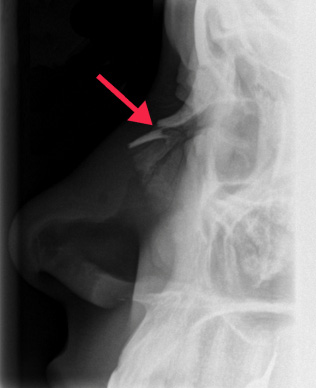

특히 코뼈는 독립적인 것이 아니라 인접한 얼굴뼈와 연결성이 크다. 따라서 코에 손상을 입었다면 X-ray나 CT 촬영 등 정밀한 검사를 통해 얼굴 전체적인 이상 유무를 확인하는 것이 좋다. 만약 검사 과정에서 코뼈골절이 밝혀지면 수술을 꼭 받아야 한다. 코골절 교정술은 간단해보이지만 정확성과 전문의의 고도의 노하우와 경험이 뒷받침 되어야 하는 쉽지 않은 수술이다.